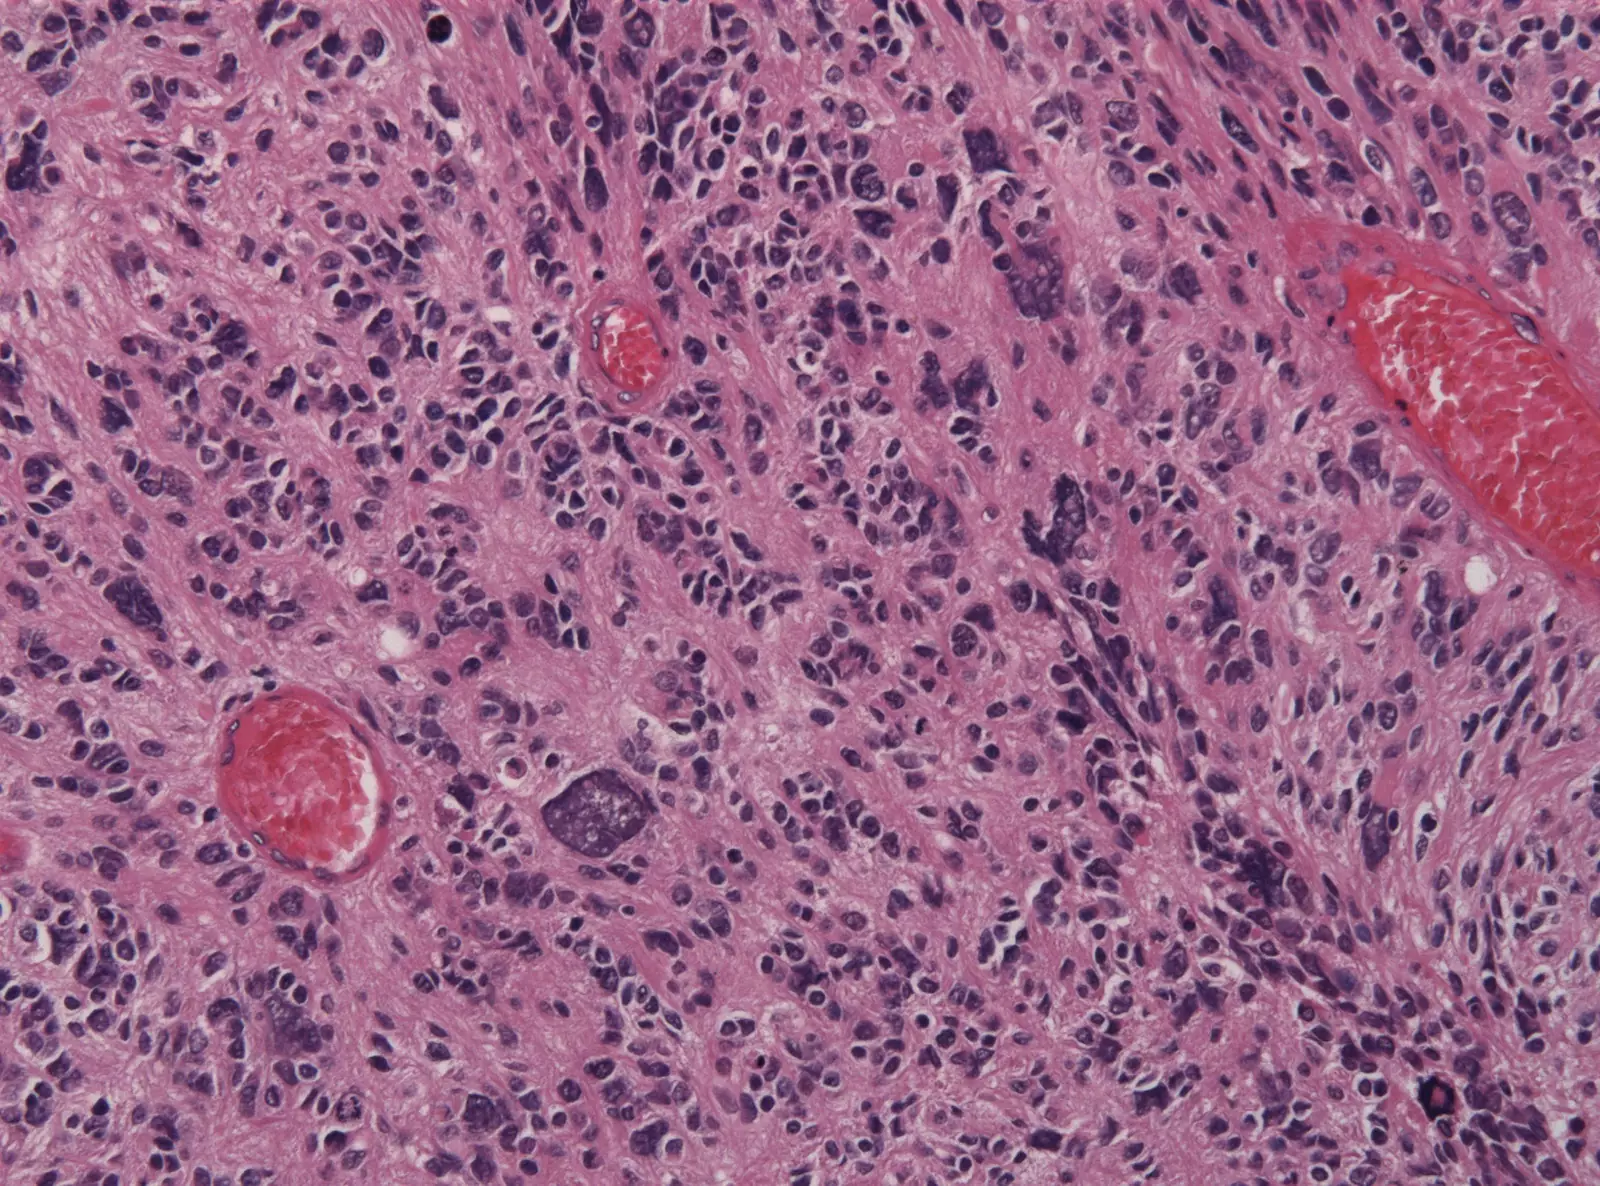

Хэнаньский университет (Китай) разработал особый тип нанокапсул, которые доставляют в мозг инструмент для редактирования генов CRISPR и лечат одну из самых агрессивных форм рака мозга — глиобластому.

В этом случае исследователи использовали CRISPR для нацеливания на ген под названием PLK1, который регулирует развитие новых клеток, а при глиобластоме действует в ускоренном режиме.